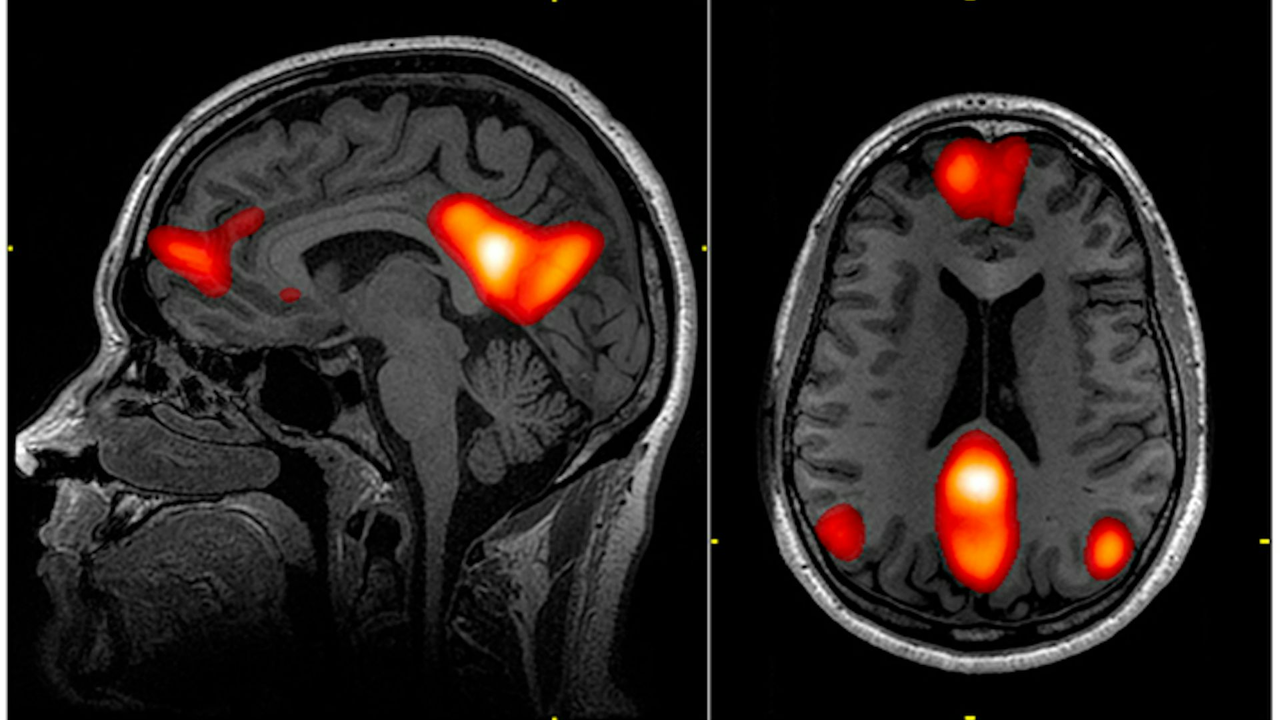

Yapılan bir çalışmada, doğada 40 dakika yürüyüş yapan bireylerin beyin görüntüleri incelendi ve stres seviyelerinde belirgin bir düşüş gözlemlendi. Aynı süreyi şehir ortamında geçirenlerde ise bu etki görülmedi.

Ayrıca, doğa görüntülerine bakarken bile amigdala (beynin stresle ilişkili bölgesi) aktivitesinin azaldığı tespit edildi.